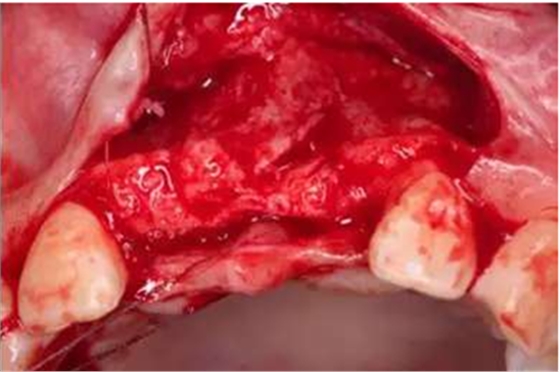

做牙槽嵴頂切口及22牙遠(yuǎn)中附加切口,翻瓣;

在11、21位置植入兩顆NobelActive 3.5mm*13mm種植體;

種植體頰側(cè)骨缺損處植入Bio-Oss骨替代品

覆蓋雙層Bio-Gide膠原膜